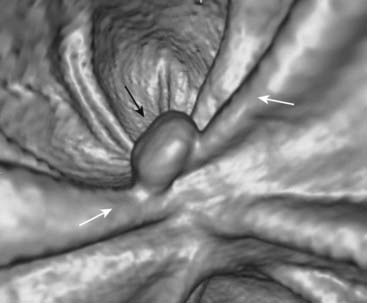

image Virtual colonoscopy is a technique made possible by newer, faster CT and MRI scanners and complex computer algorithms that allow for the three-dimensional reconstruction of the appearance of the inside of the bowel lumen including time-of-flight (motion) displays without the use of an endoscope. Virtual colonoscopy also allows for visualization of the other abdominal structures outside of the colon (Fig. 18-15).

Figure 18-15 Polyp on virtual colonoscopy.

Virtual colonoscopy utilizes CT scanning of the abdomen to allow for the three-dimensional reconstruction of the appearance of the inside of the bowel lumen without the use of an endoscope. A polyp in the descending colon (solid black arrow) is seen as a distinct mass, while the normal haustral folds (solid white arrows) are ridgelike structures present throughout the large bowel.